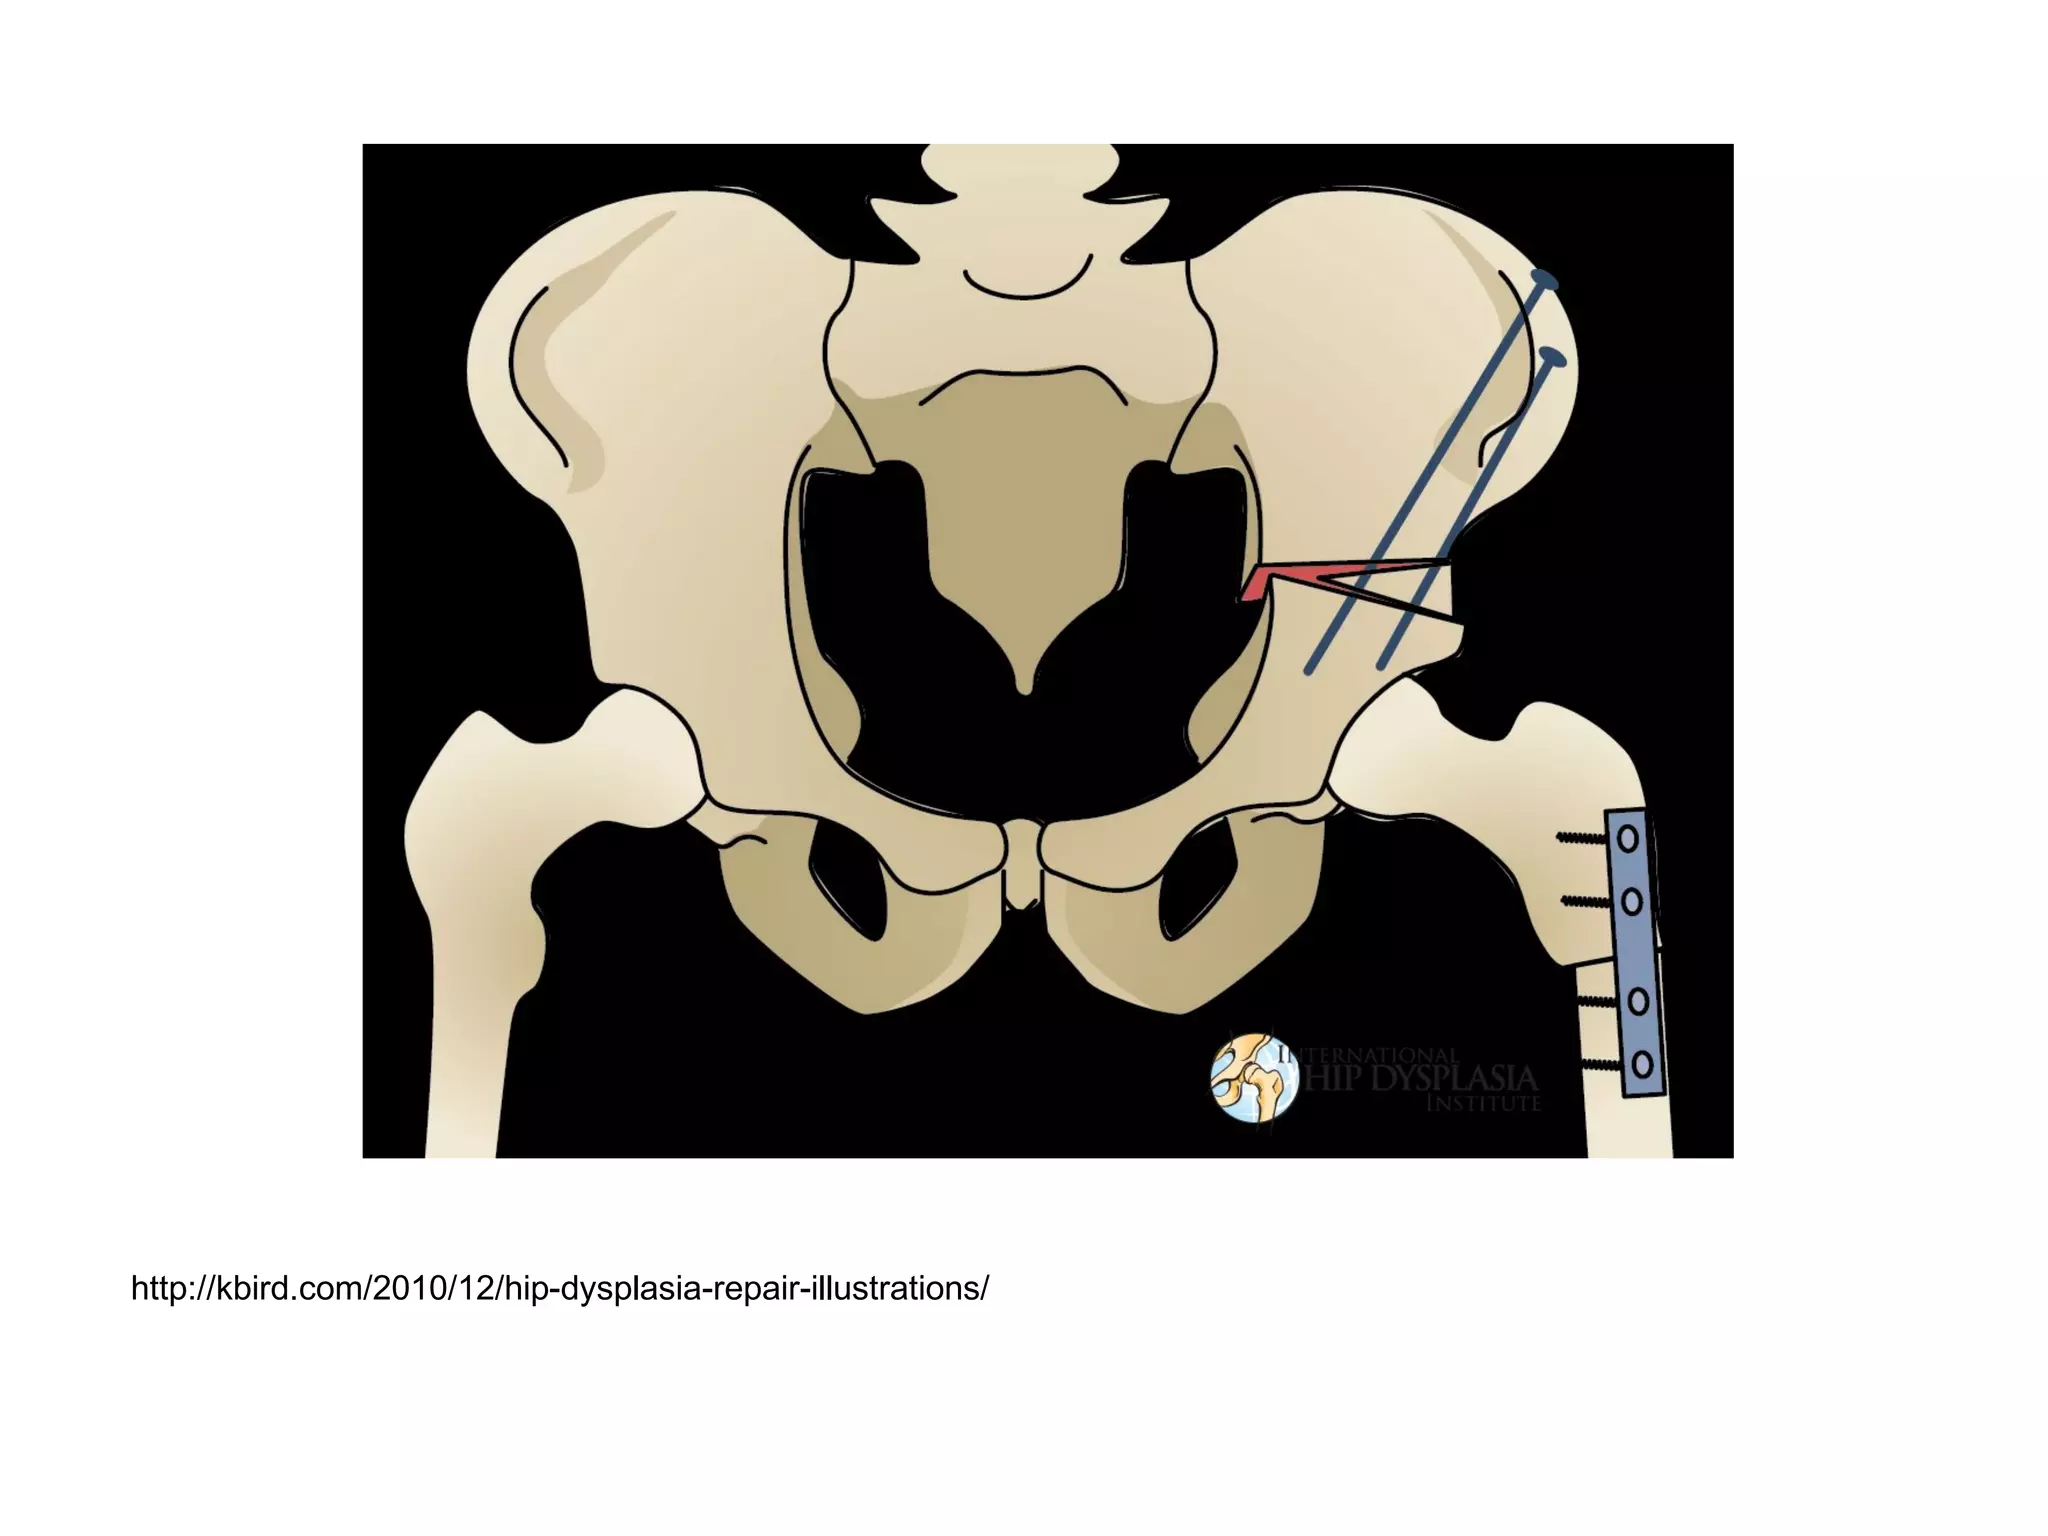

Varus osteotomy of the femur

Open Reduction, Pelvic Osteotomy, Femoral Shortening and Varus Osteotomy -

See more at: http://hipdysplasia.org/developmental-dysplasia-of-the-hip/child-treatment-

methods/osteotomy/#sthash.BArftDsO.dpuf

http://hipdysplasia.org/developmental-dysplasia-of-the-hip/child-treatment-methods/osteotomy/

http://kbird.com/2010/12/hip-dysplasia-repair-illustrations/